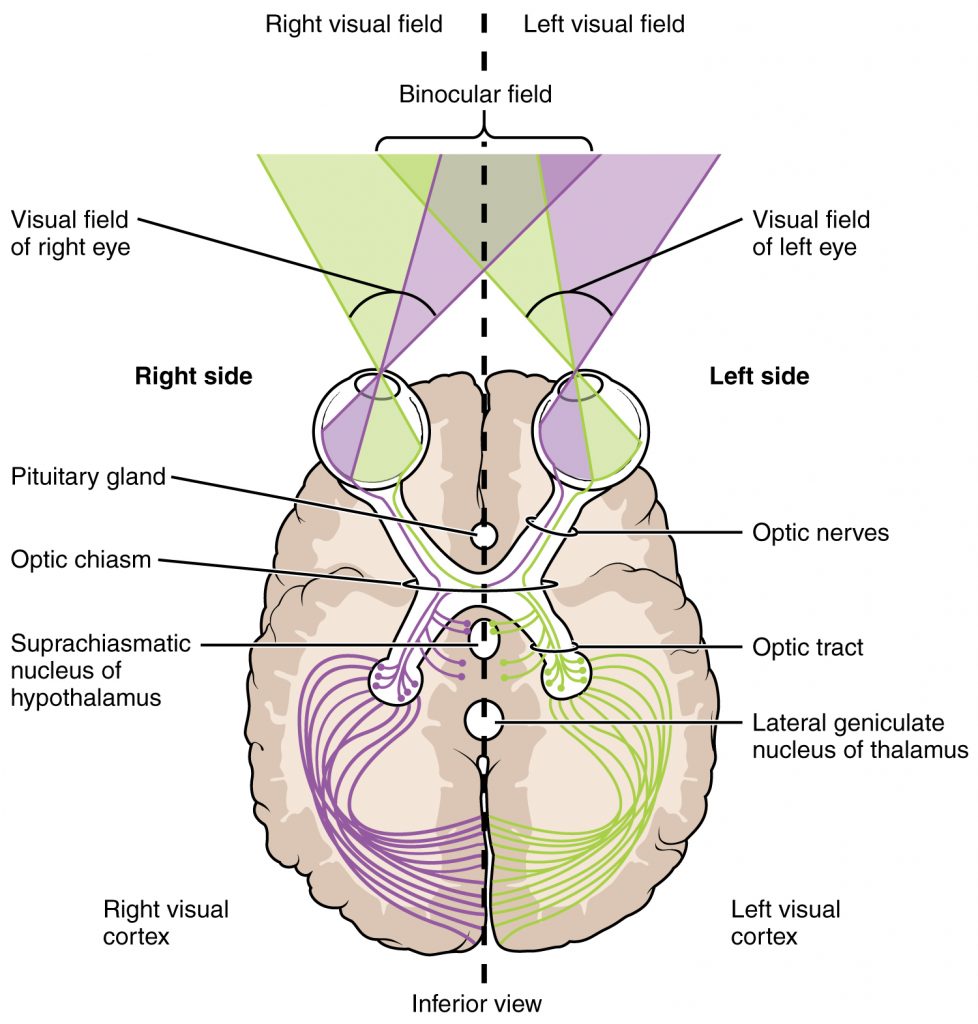

Comme vous le savez, les informations de chaque côté du corps vont au côté opposé du cerveau, connu sous le nom d’organisation controlatérale du cerveau. Lorsque le stimulus est représenté sur la moitié droite de l’écran, les informations sont transmises à l’hémisphère gauche. Le centre de la parole étant situé dans l’hémisphère gauche, dans le cerveau de la plupart des gens, le patient peut nommer le stimulus. D’autre part, lorsque le stimulus est représenté sur le côté gauche de l’écran, les informations sont transmises à l’hémisphère droit, où il n’y a pas de centre de la parole, il n’est donc pas possible de nommer le stimulus.